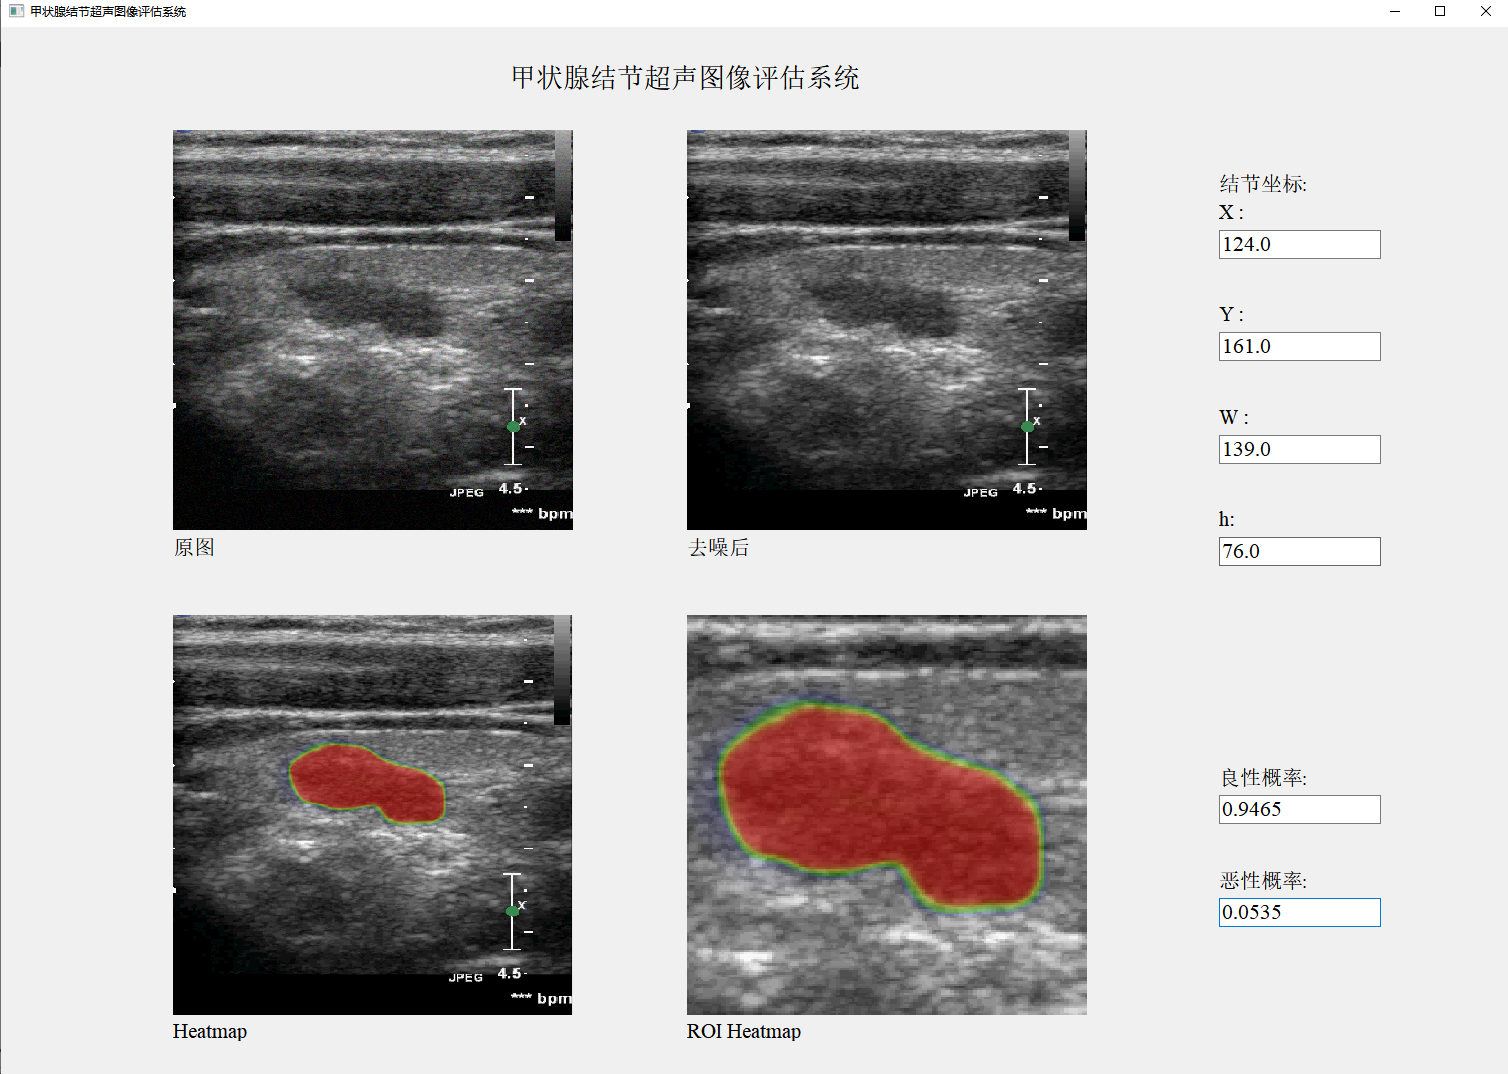

[6] Jianning Chi*, et al. Thyroid Nodule Classification in Ultrasound Images by Fine-Tuning Deep Convolutional Neural Network, Journal of Digital Imaging, 2017, 30(4): 477-486. (中科院2区期刊,IF: 4.4)

[10] 迟剑宁*, 于晓升, 张艺菲. 融合深度网络和浅层纹理特征的甲状腺结节癌变超声图像诊断,中国图象图形学报, 2018, 23(10): 1582-1593. (中文核心期刊)

[1] 吴成东, 张艺菲, 迟剑宁. 一种基于深度学习网络和浅层纹理特征融合的甲状腺超声图像结节分析方法. 中国专利, CN110211116A, 2019.9.6.

[1] 迟剑宁, 吴博, 吴慧璇, 林庚, 凌修伟. 甲状腺多模态影像自监督软件v1.0. 计算机软件著作, 2025SR0182374, 2025.1.26.

[3] 迟剑宁, 吴慧璇, 林庚, 凌修伟, 吴博. 基于双分支跨模态注意网络的甲状腺超声图像结节诊断软件v1.0. 计算机软件著作, 2025SR0188545, 2025.1.27.